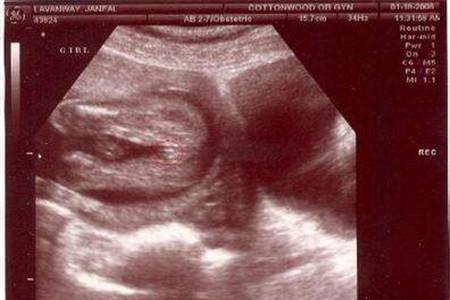

一般怀孕两个月肚子的大小还看不太很出来,一般起码三个月以后才会感觉到肚子变化比较大,有的孕妇就是显怀比较早,差不多两三个月的时候就可以看出突起的小肚子了,可以去做B超检查一下。